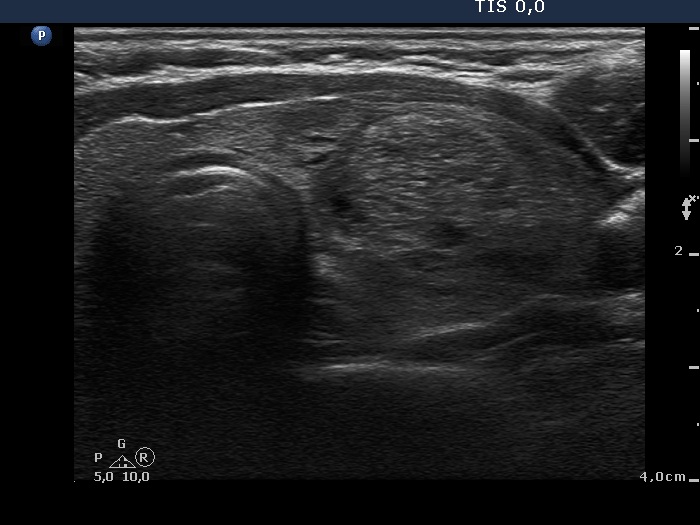

Benign nodular hyperplasia - Case 51. (ultrasonographic picture 5)

Right lobe, longitudinal scan

Left lobe, another horizontal scan. There is a relatively large echonormal nodule presenting fibrosis and non-specific hyperechogenic figures.